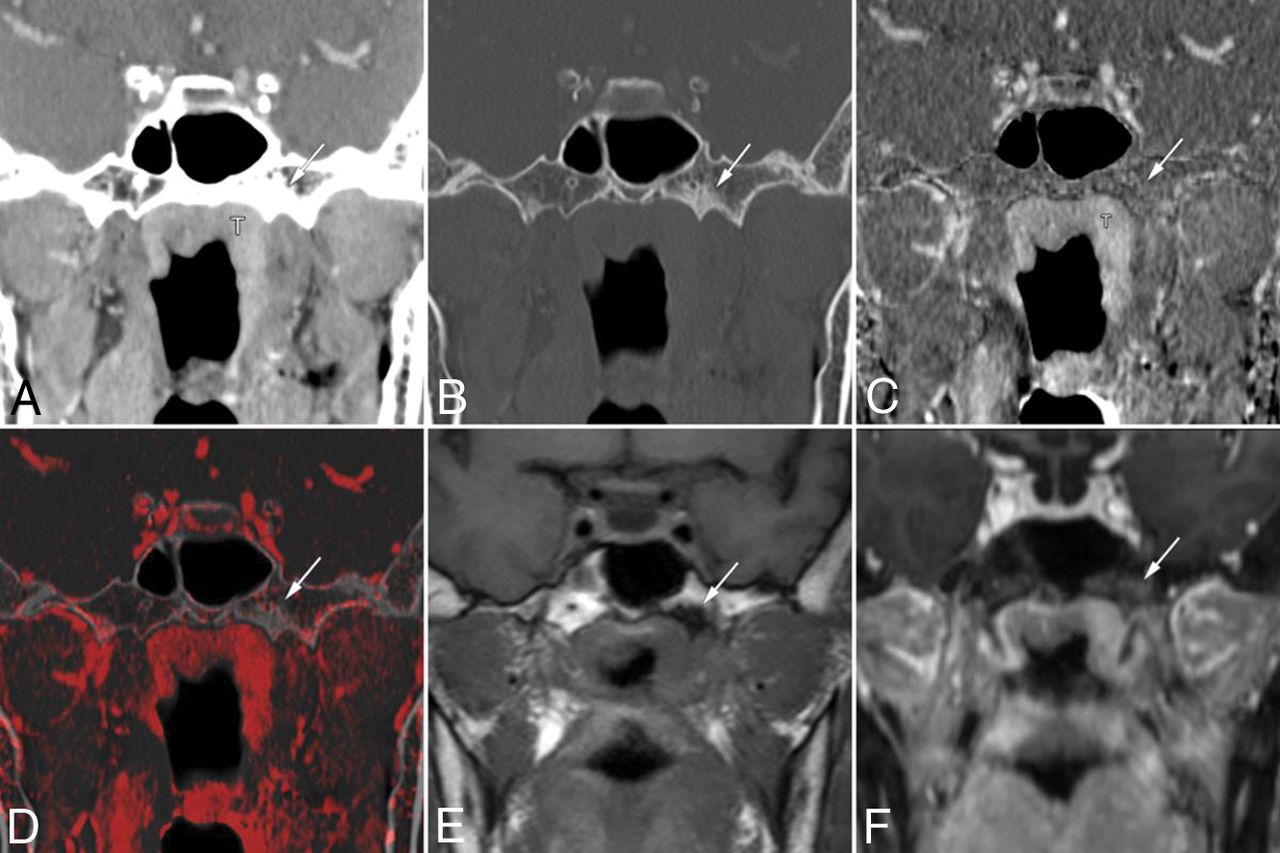

False-positive findings at the base of the left pterygoid process on conventional CT images alone in a 63-year-old woman with nasopharyngeal carcinoma. Coronal contrast-enhanced CCT images (A, soft-tissue window; B, bone window) show nasopharyngeal tumor (T) and bone sclerosis at the left base of the pterygoid process (arrow). The case was given a score of 3 based on CCT images alone. Bone subtraction iodine image (C) and color fusion image (D) clearly show no enhancement in the sclerotic area (arrow). E, A corresponding slice on the T1-weighted image shows low signal intensity due to sclerosis (arrow). F, Fat-suppressed T1-weighted images after gadolinium administration show contrast enhancement of the tumor mass and poor enhancement of the pterygoid process (arrow). This was considered a case of clinical T2 category disease without skull base invasion and was treated by chemoradiotherapy.